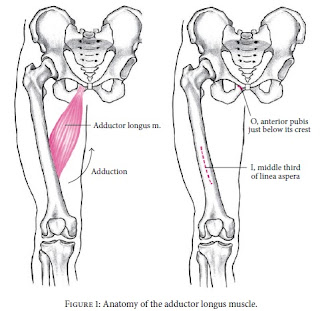

O adutor longo é um músculo longo e relativamente estreito,

de forma triangular. O músculo tem origem no ramo superior do osso púbico e insere-se

na parte média da linha áspera do fémur. As fibras musculares são estreitas na

origem e espalham-se mais para a inserção.

O ramo anterior do nervo obturador inerva este músculo. E a

sua função é a adução, rotação externa e anteversão da articulação da anca.